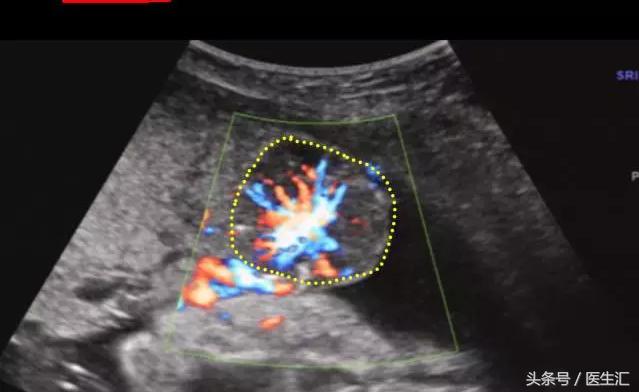

超声检查提示:宫底后壁胎盘与后壁肌层之间见混合回声区(超声表现1,见图1黄色圈内),与胎盘分界不清,范围约75mm×34mm,内回声不均匀,边缘及内部未见明显血流信号(检查要点1)。急诊剖宫产手术见胎盘80mm×50mm剥离面,占1/2(超过胎盘面积的1/3),宫腔积血约50ml,术后诊断胎盘早剥。

(图1)